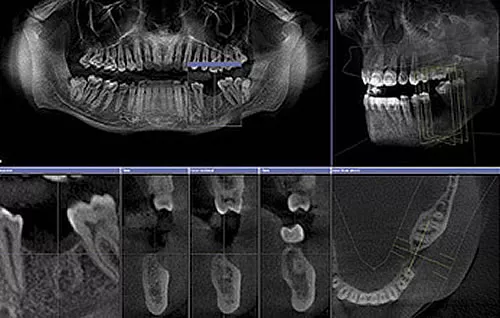

Das 3D-Röntgen – auch bekannt als Digitale Volumentomographie (DVT) – ist ein modernes bildgebendes Verfahren, das hochpräzise, dreidimensionale Aufnahmen von Kiefer, Zähnen, Knochensubstanz und umliegenden Strukturen liefert. In nur wenigen Sekunden entsteht ein volumetrisches Bild, das eine vollständige räumliche Analyse ermöglicht.

Dank dieser Technologie können Zahnärzte komplexe Behandlungsfälle präzise beurteilen und gezielt planen. Die 3D-Bilder helfen dabei, krankhafte Veränderungen, anatomische Besonderheiten oder kritische Strukturen wie Nervenverläufe exakt zu identifizieren.

Digitale Volumentomographie (DVT) – hochauflösende 3D-Röntgentechnik für präzise Zahn- und Kieferdiagnostik in der ACC Zahnklinik Basel

3D-Röntgen – moderne Bildgebung für detaillierte Darstellung von Zähnen und Kiefer in der ACC Zahnklinik Basel